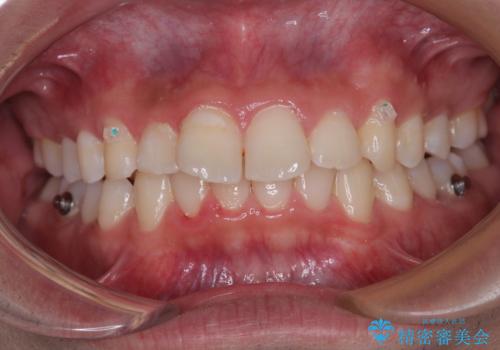

デコボコをインビザライン矯正で改善 奥歯は補助装置で確実に移動を

- ディープバイトと上顎前歯の突出、奥歯の咬み合わせを気にして来院された患者様です。

上顎歯列は全体的に前方位にあり、それが原因で深い咬み合わせとなり、突き上げにより上顎前歯が前方に飛び出している状態でした。

また、左右ともに上顎最後臼歯が頬側に転位している鋏状咬合となっていました。

インビザラインによる矯正治療をご希望でしたが、上顎歯列の前方位と鋏状咬合を確実に改善することを目的として、補助装置を併用することとしました。

補助装置を併用せずに治療を終える可能性はありましたが、確実に結果を得るために補助装置を活用しました。

イメージしたとおりの仕上がりとなりました。